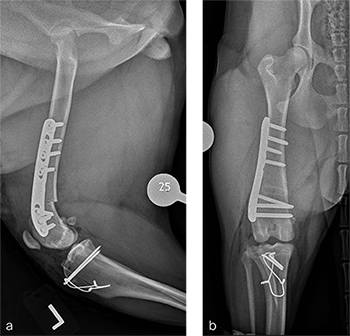

A routine lateral approach to the distal femur and stifle joint was performed. Results of the cruciate ligaments examination were normal. The lateral joint capsule was dissected to expose the distal femoral condyle. An alignment jig was placed in a craniocaudal direction to ensure that deformity correction was limited to the frontal plane. A 12 lateral closing wedge ostectomy was performed and the femoral condyle was reduced and temporarily stabilized with divergent K-wires. A 7-hole left 3.5 LCP DFO plate was placed on the lateral femur and secured with a combination of 3.5 mm cortex and locking screws. The compression function of the plate was used to compress the ends of the two bone segments. Temporary K-wires were removed and a wedge sulcoplasty was performed to deepen the trochlear groove for improved patella articulation. A tibial tuberosity transposition was performed and stabilized with two pins and tension band wire. Routine closure was performed. Total surgical time was 1 hour and 45 minutes. Postoperative x-rays demonstrate the position of a left, 7-hole, 3.5 LCP DFO plate and associated tibial tuberosity transposition. In the medioateral view it can be appreciated that plate contour matches the normal distal femoral procurvatum and screws are positioned caudally away from the trochlea (Fig 6a). This allows for an unimpeded sulcoplasty while maximizing screw purchase caudally. The compression applied with the plate has resulted in excellent apposition. The patella is visible within the trochlear groove. In the craniocaudal view the plate contour matches the anatomical contour of the distal femoral condyle (Fig 6b). The anatomical Lateral Distal Femoral Angle is reduced to 92. During the follow up after 8 weeks, clinical signs have resolved, limb use is excellent, and stifle joint range of motion is normal without evidence of pain. In the mediolateral x-ray the osteotomy has healed (Fig 7a). Plate and screw position remain unchanged. The tibial tuberosity transposition is healing, and implants remain unchanged. The patella remains reduced within the trochlear groove. In the craniocaudal view the osteotomy has healed and is no longer visible (Fig 7b). Implants are stable and the patella is tracking normally.